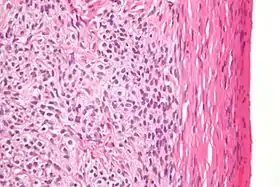

![]() صورة مجهرية للورم القرابي بصبغة الهيماتوكسيلين والأيوزين صورة مجهرية للورم القرابي بصبغة الهيماتوكسيلين والأيوزين | |

عيانياً الورم صلب أصفر اللون، يتكون من قشرة المبيض.

ومجهرياً، يمتلئ السيتوبلازم بالليبيدات.